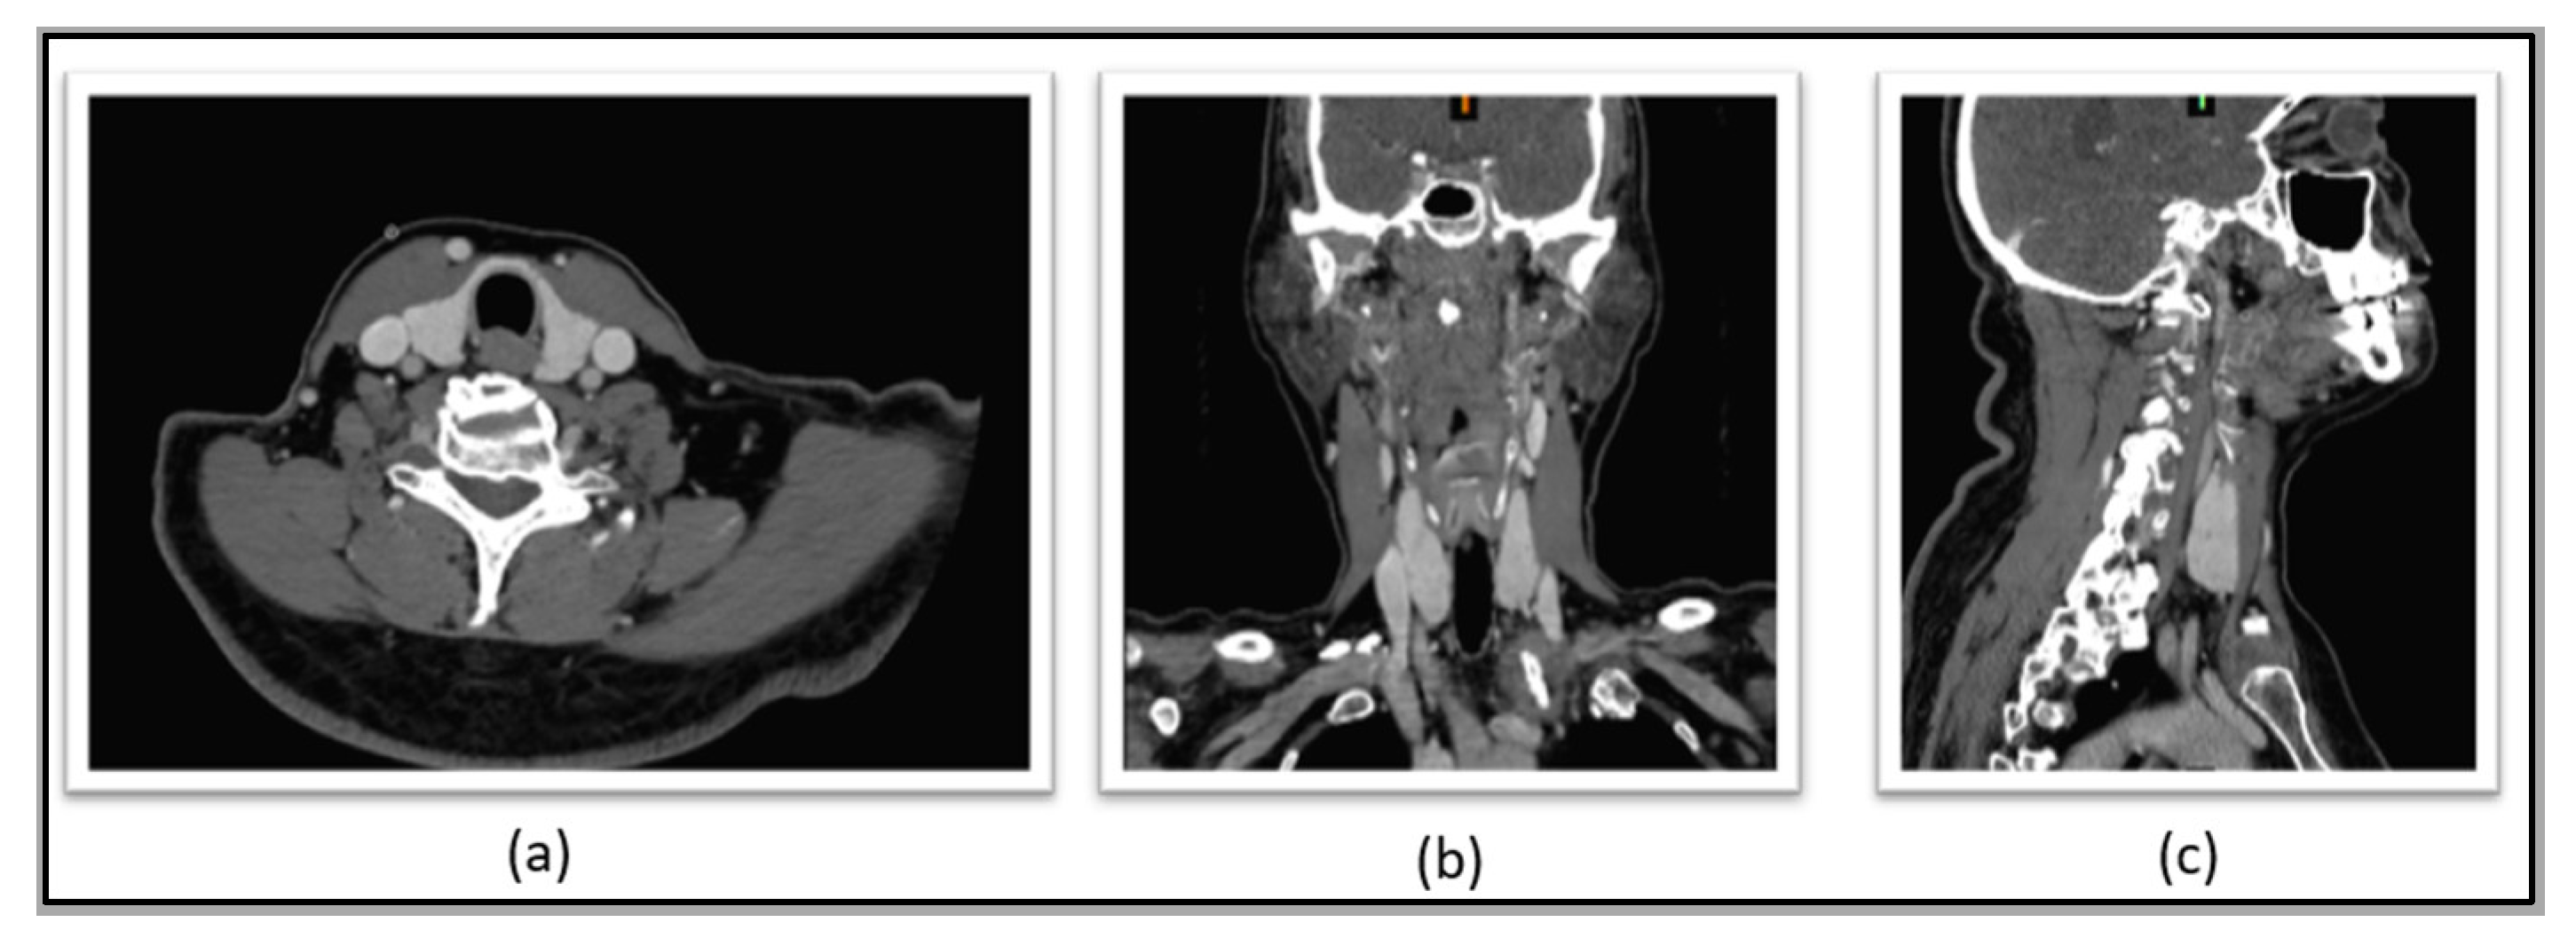

Complementing the clinical protocol, patients underwent the acquisition of anatomical images (which can be either magnetic resonance imaging (MRI) or computerized tomography (CT)). To illustrate, Figure 2 shows some of the individual anatomical imaging planes (axial, coronal, and sagittal) obtained through the CT system. The CT equipment used in this research was a GE Optima CT660, with 64 channels, which allows acquisitions of 40 mm, providing isotropic images of 0.35 mm of spatial resolution. Additionally, for this CT acquisition, an iodine contrast is injected into the patient, so the thyroid gland is more evident in the images since the grayscale is better differentiated among the different anatomical structures.

Figure 2.

Thyroid seen in differentiated grayscale, which is shown in: (a) axial, (b) sagittal and (c) coronal.